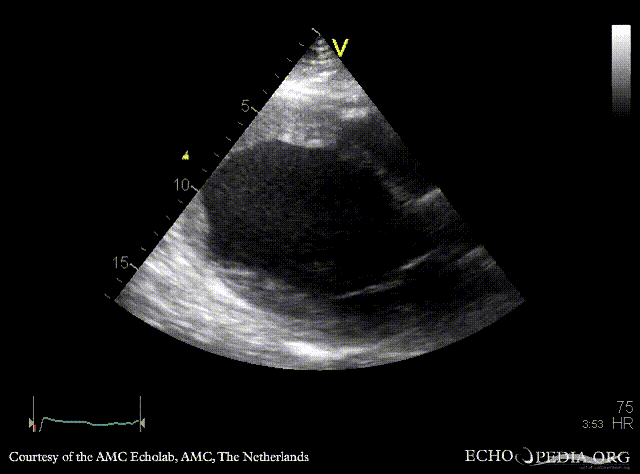

E00217.gif E00218.gif

PLAX: dilated left ventricle with poor function PSAX: dilated left ventricle with poor function, spontaneous echo contrast